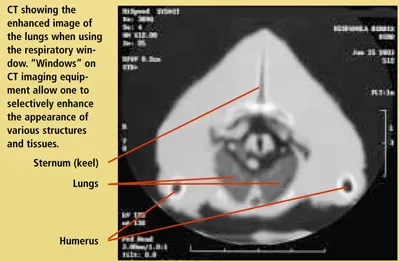

The avian respiratory system is extensive and complex. Becoming familiar with the normal presentation of respiratory anatomy through use of different imaging techniques will enhance a clinician's ability to make a diagnosis. This is the first of two articles using radiographic images and computed tomography (CT) to compare normal respiratory structures of the avian respiratory system. Note that the size of the patient dictates the size of the CT image. In this case, the patient is very small; thus, the images have become somewhat blurry with enlarging. Nevertheless, contrast is an important factor in CT imaging and the structures are quite clear. This article focuses on the body; the next part will address the head. For larger images, please click on the PDF icon at the top of the page to download the print version of the article in its entirety.